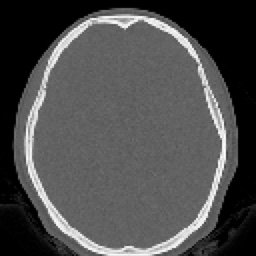

SIMPLE FINO (4) 129 images

HUESO FINO (5) 129 images

ARTERIAL FINO (7) 129 images